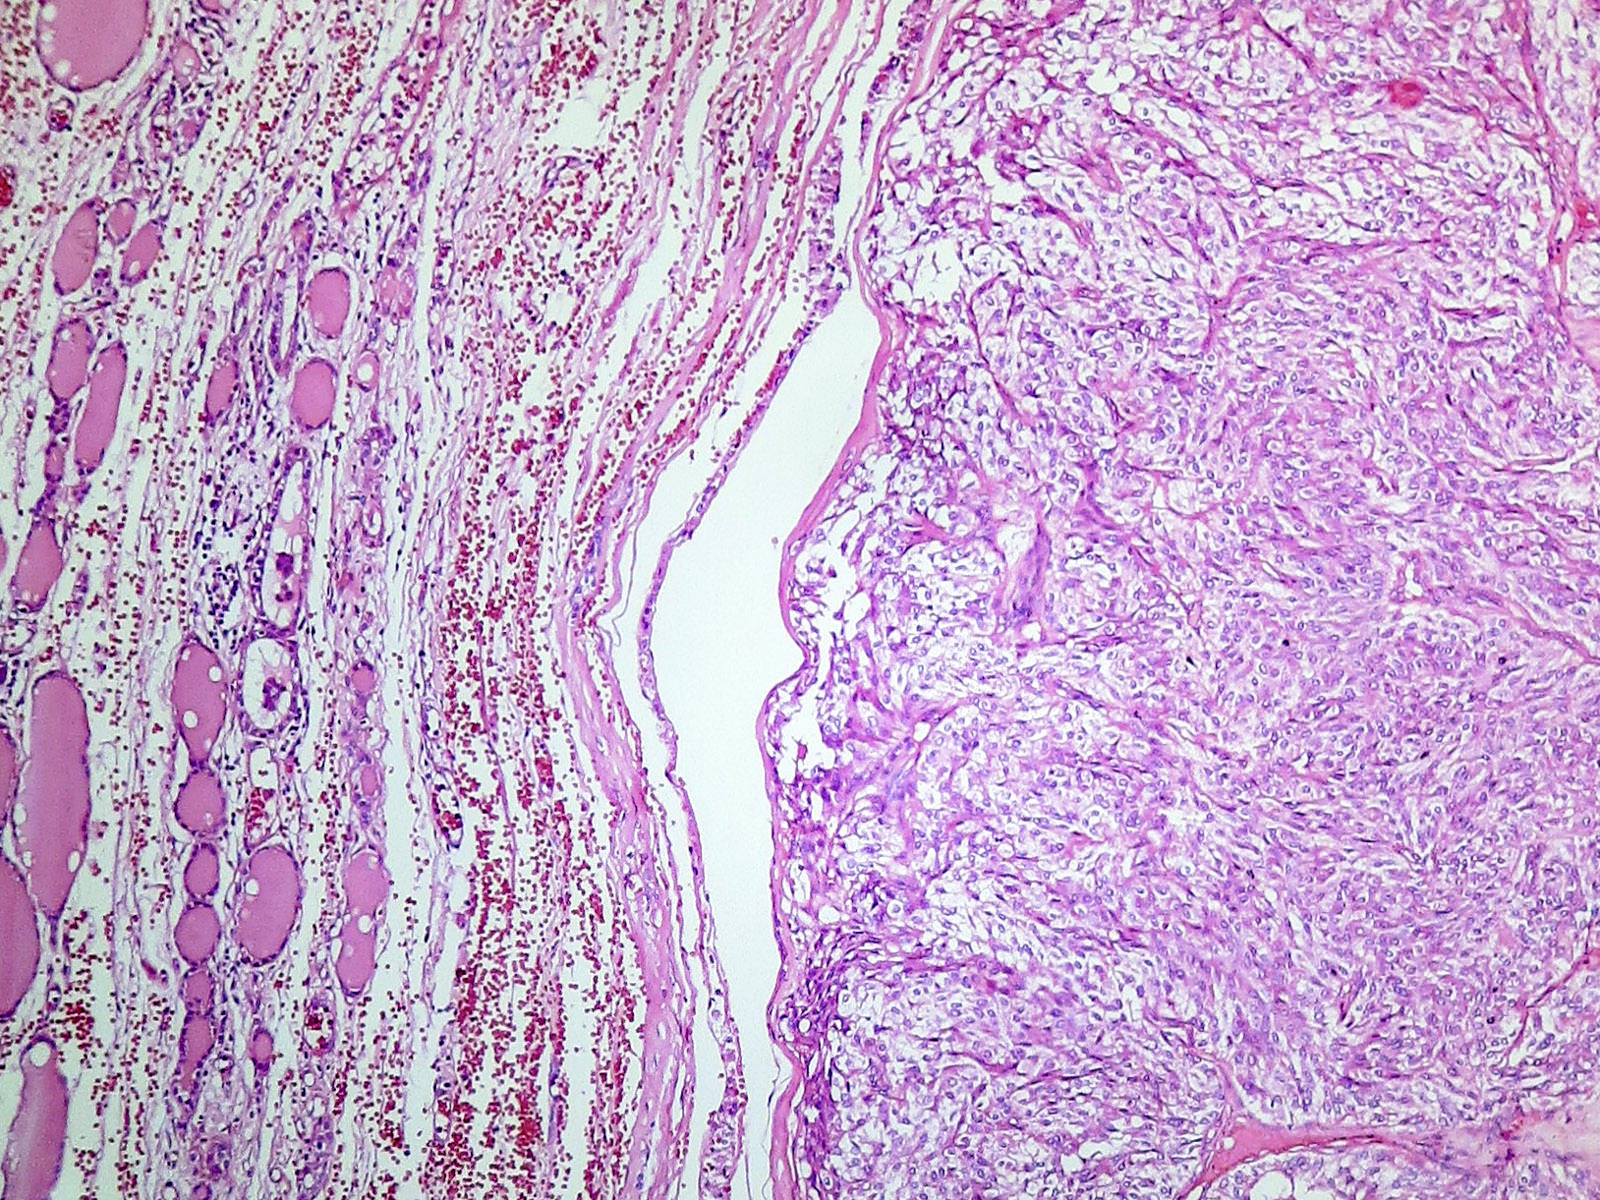

Microscopic (histologic) description

- Wide variety of morphology, can mimic any other thyroid malignancy

- Round, plasmacytoid, polygonal or spindle cells in nests, cords or follicles; often mixtures of these cells

- Round nuclei with finely stippled to coarsely clumped chromatin and indistinct nucleoli, occasional nuclear pseudoinclusion

- Eosinophilic to amphophilic granular cytoplasm due to secretory granules

- Generally low mitotic figures

- Stroma has amyloid deposits from calcitonin, prominent vascularity with glomeruloid configuration or long cords of vessels (Am J Surg Pathol 1995;19:642), coarse calcifications, occasional psammoma-like bodies

- Mucin in 42% (Arch Pathol Lab Med 1983;107:70)

- Often angiolymphatic invasion

- Occasionally marked neutrophilic infiltrate, oncocytic tumor cells, papillary patterns

- May entrap follicles

- C cell hyperplasia present in familial but not sporadic cases

Microscopic (histologic) images

Contributed by Shuanzeng Wei, M.D., Ph.D., Joseph Christopher Castillo, M.D. and Mark R. Wick, M.D.